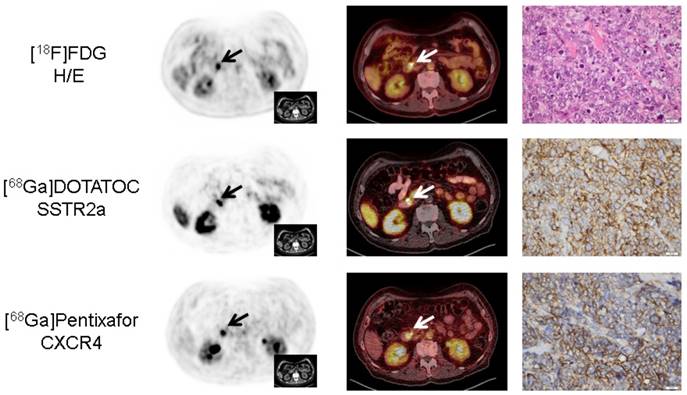

Figure 3

Concordance of immunohistochemistry and non-invasive receptor-directed PET imaging in a patient with pancreatic neuroendocrine tumor (NET; patient #3; Ki67: 85%). Display of transaxial PET (left) and fused PET/CT (middle) images of the primary tumor in the major pancreatic papilla (papilla of Vater; papilla vateri). The NET demonstrates high expression of both SSTR2a and CXCR4 which could be confirmed in the surgical specimen after tumor resection (right). Interestingly, CXCR4-PET correctly identified three additional lymph node metastases (versus none in [18F]FDG- and a single metastasis in SSTR-directed PET, Supplementary Figure 1). All PET/(CT) images are displayed identically with a window level between 0 and 5.5. [18F]FDG = 18F-fluorodeoxy-glucose, [68Ga]DOTATOC = 68Ga-DOTA-D-Phe-Tyr3-octreotide.